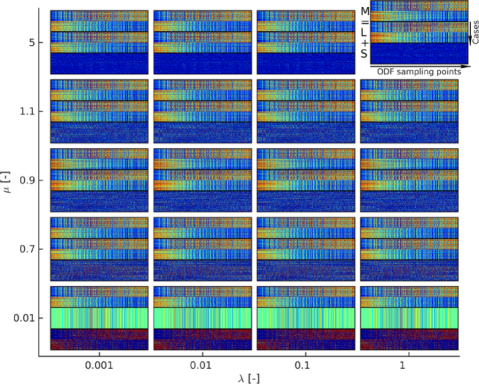

The -matrix decomposition solved using the noncvxRPCA-algorithm has two main tunable parameters: (Eq. 1) and , a Lagrange penalty parameter. The parameter balances and in (1), a higher will put more emphasis on the sparsity of while a lower will force the rank of down. Although the outcome of (1) could be expected to depend on the choice of , it was shown mathematically that a whole range of values ensure the exact recovery of and (Candes et al., 2011). A universal choice of with and , the dimensions of has been suggested (Candes et al., 2011; Lin et al., 2010) and successfully applied in a large number of applications. We have employed in this work when observing 321 vertices per ODF and 350 subjects, though a wide range of performs as desired (Fig. 2).

The variable in the augmented Lagrange multiplier optimization approach is the penalty parameter for the violation of the linear constraint during the search. Simulations (Fig. 2) suggest that a large enforces a very sparse whilst a small decreases the rank of . Hence it is important to select an appropriate value of for our application. Here, we have chosen to use in accordance with literature (Kang et al., 2015). Indeed, simulations (Fig. 2) show that values of in a range around 1 balance the sparsity of with the rank of as desired.

Using the decomposition (Eq. 1) means that a choice for the balance parameter and the Lagrange penalty parameter has to be made. Choosing is straightforward as a universal choice is suggested by theoretical considerations (Candes et al., 2011; Lin, 2016). Simulations furthermore show that the decomposition is relatively insensitive to (Fig. 2). An appropriate value for will however have to be found heuristically. While our results were stable for in range around 1, it is clear that the extraction of essential ODF features will suffer when is too small (too few ODF features in L) or too large (too much individual variability in L) (Fig. 2).